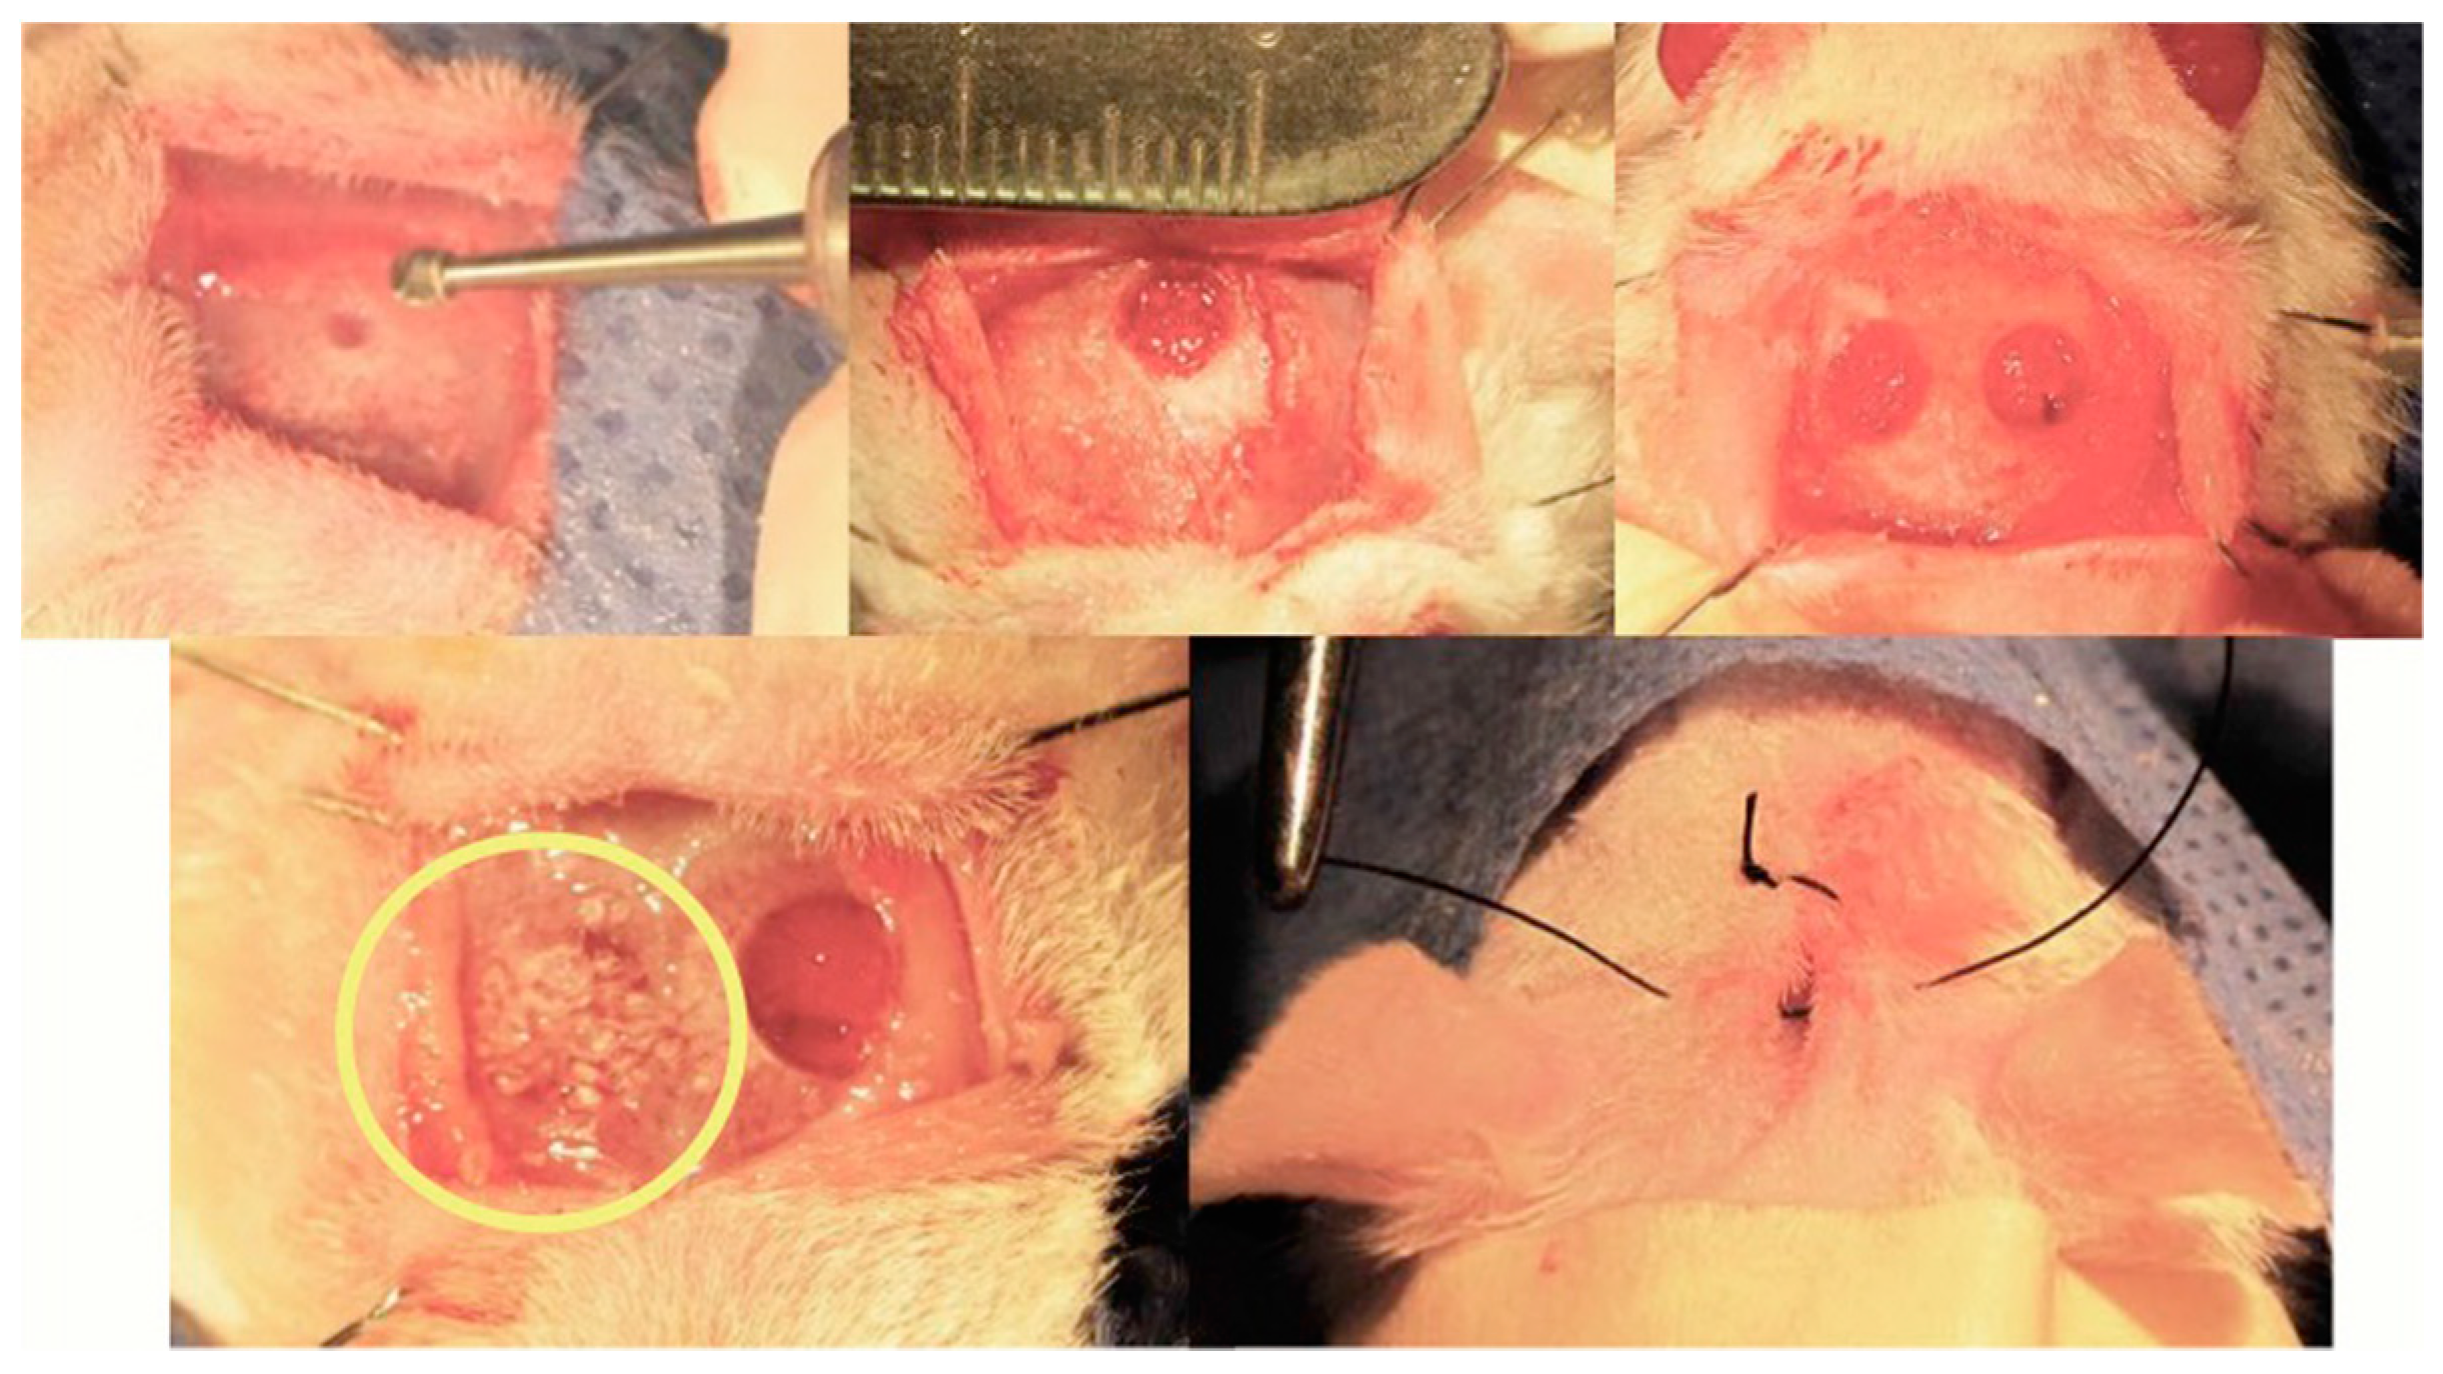

7.3. Rat Calvarial Defect Model and Implantation of the Scaffold